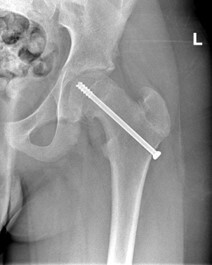

- Fissazione in situ. Questa è la tecnica utilizzata più spesso per i pazienti con epifisiolisi stabile o lieve. Il chirurgo effettua una piccola incisione vicino all'anca, inserisce una vite metallica attraverso la piastra di crescita (fisi) per mantenere la posizione della testa del femore e prevenire altri slittamenti (fig. C). Nel tempo, la piastra di crescita si chiuderà. Una volta che la piastra di crescita è chiusa, non si possono verificare scivolamenti;

Fig C Fissazione della testa del femore con l’utilizzo di una vite.